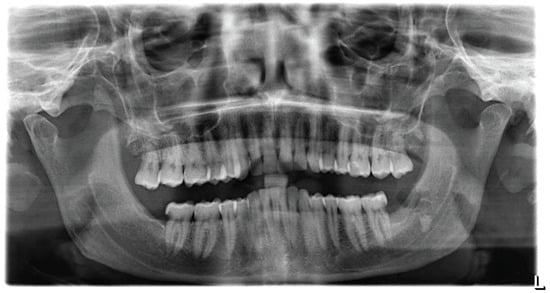

2.4. Radiographic Documentation